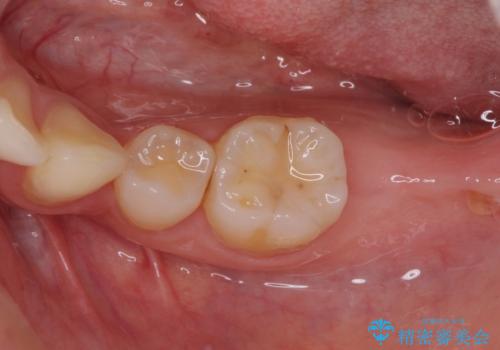

右下の歯は、レントゲン上歯髄組織まで虫歯が及んでいるように見えましたが、痛みの症状は強くなかったため、歯髄組織の一部を断ち歯根部分の組織を保存する生活歯髄療法を第一選択に処置を進めて行くこととしました。

まず生活歯髄療法を行い、その後部分矯正やインプラント処置を行いましたが、最初の処置から1年以上経っても右下奥の処置歯の神経組織に異常は認められませんでした。